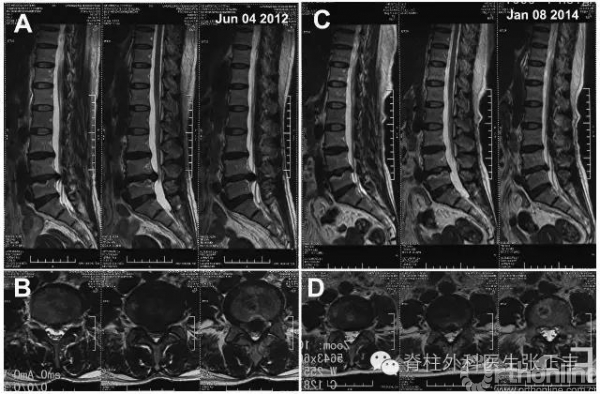

2.腰椎间盘突出症融合手术

复发率只有7%哦!

腰椎间盘髓核摘除术还是腰椎椎间盘突出症手术治疗的金标准。(尽管经皮内镜椎间盘髓核摘除术(PELD)或显微椎间盘髓核摘术还有争论。)

腰椎间盘突出症融合手术适应证:伴腰椎不稳;伴腰椎管狭窄;伴终板炎II级;巨大型椎间盘突出症(马尾综合征);术后复发;惧怕复发率为7%的患者等。